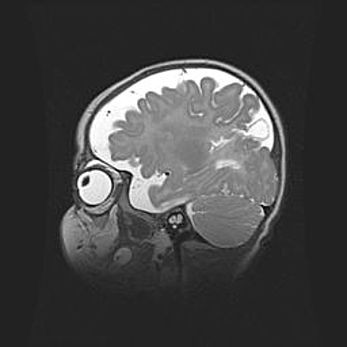

Церебральная ишемия II.

Возраст: 5 дней

Вес: 3400 г

Пол: женский

Окружность головы: 35 см

Срок гестации: 39 недель

Церебральная ишемия – это заболевание, характеризующееся недостаточностью (гипоксией) либо полным прекращением (аноксией) снабжения мозга кислородом по причине закупорки одного или нескольких сосудов. Это приводит к  что метаболическим расстройствам различной степени тяжести в тканях головного мозга, развитию коагуляционных некрозов и гибели нейронов.